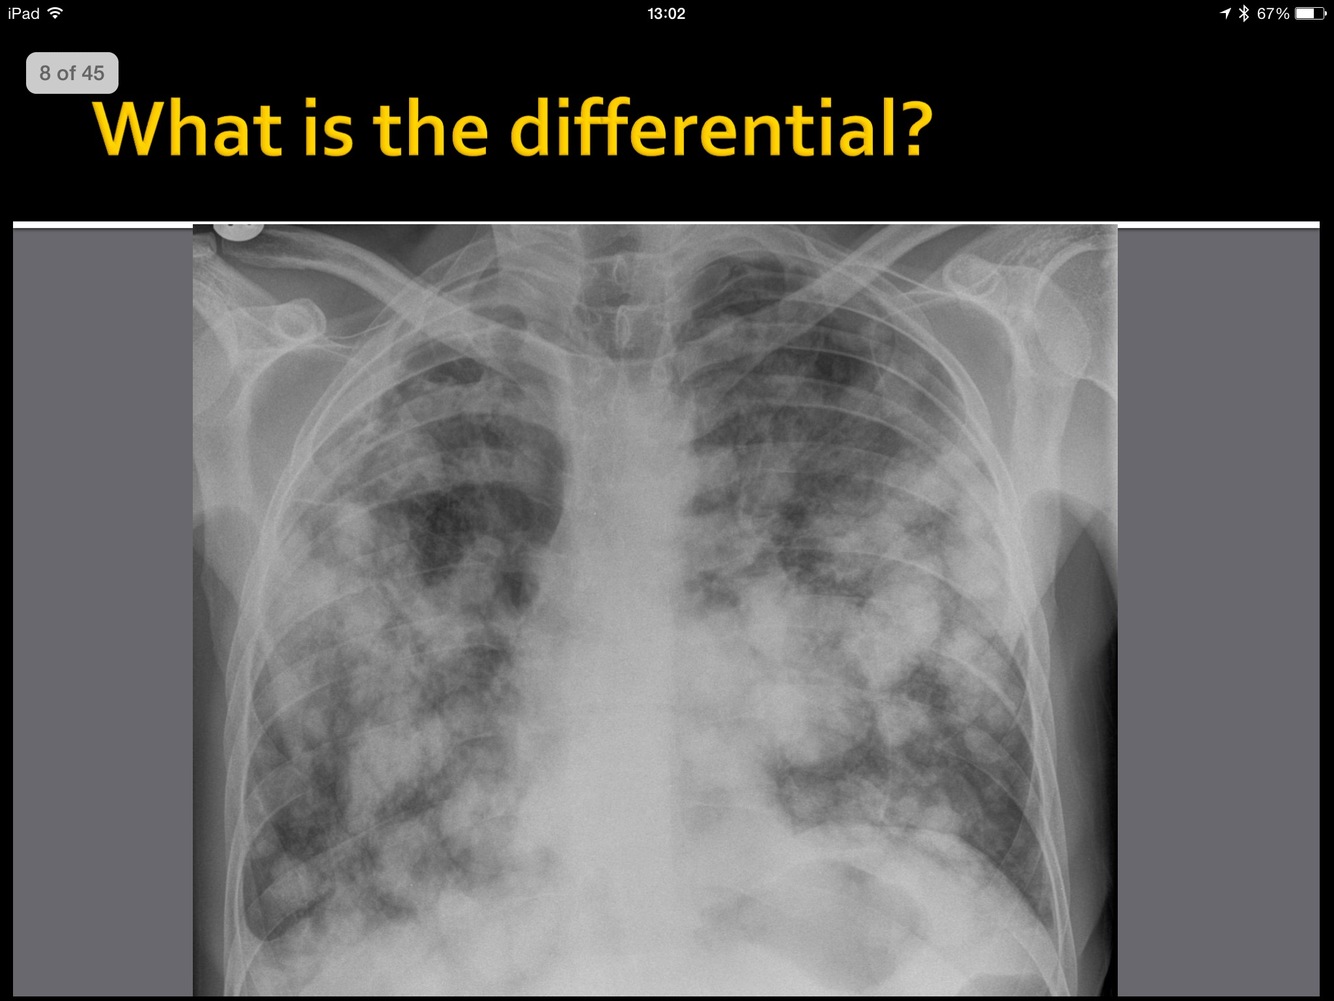

whatis the abnormality?